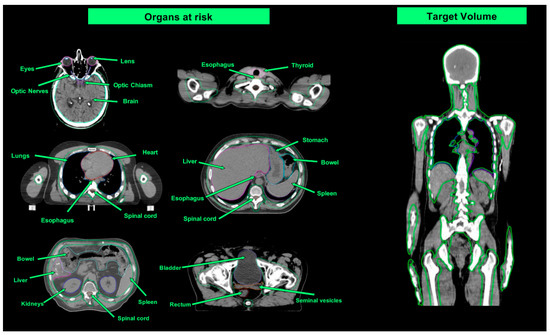

4.1. Planning

4.3. Treatment Delivery

| Organ at Risk | TBI Median Doses (Gy) | Studies Evaluating TMI/TMLI Median Doses (Gy) | ||

|---|---|---|---|---|

| Wong et al. [51] (TBI 12 Gy) | Wong et al. [51] (TMI/TMLI 12 Gy) | Wong et al. [51] (TMI/TMLI 20 Gy) | Our Case (TMLI 12 Gy) | |

| Brain | 12.0 | 4.0 | 7.9 | - |

| Lens | 11.3 | 1.5 | 1.9 | 1.7 |

| Eyes | 11.3 | 6.6 | 7.0 | 5.7 |

| Optic nerves | 12.4 | - | - | - |

| Oral cavity | 11.8 | 3.9 | 4.8 | 8.5 |

| Parotids | 11.8 | 3.9 | 4.8 | 9 |

| Thyroid | 12.1 | 3.7 | 4.9 | 3.9 |

| Esophagus | 12.4 | 3.9 | 5.6 | 11.7 |

| Breasts | 11.5 | 6.9 | 8.7 | - |

| Lungs | 8.9 | 4.3 | 6.8 | 7.7 |

| Heart | 12.1 | 6.2 | 6.4 | 6.1 |

| Stomach | 12.2 | 3.1 | 5.0 | 5.5 |

| Small Intestine | 12.5 | - | - | 5.7 |

| Liver | 12.3 | 6.0 | 8.7 | - |

| Kidneys | 12.2 | 5.6 | 8.7 | 5 |

| Bladder | 12.4 | 7.0 | 7.4 | 6 |

| Rectum | 12.6 | - | - | 5.9 |